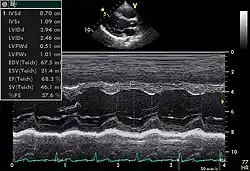

Le cœur est un organe tridimensionnel mobile. La prise en compte de cette quatrième dimension (le temps) est nécessaire pour une bonne appréhension de l'organe dans sa globalité. Cela nécessite une résolution temporelle suffisante pouvant être caractérisée par la cadence d'acquisition des images : elle doit être au moins d'une vingtaine images/s et idéalement supérieure à 50 images/s (pour permettre une visualisation correcte en ralenti, surtout si la fréquence cardiaque est élevée). De même, l'analyse à l'aide d'une image, par essence, bidimensionnelle, d'un organe quadridimensionnel, impose certains artifices : c'est le mode Tm (pour l' anglais : time motion), utilisé de manière courante, avec en abscisse le déroulement du temps et en ordonnée les échos détectés sur une seule ligne de tir.

- On en mesure les diamètres en systole et en diastole.